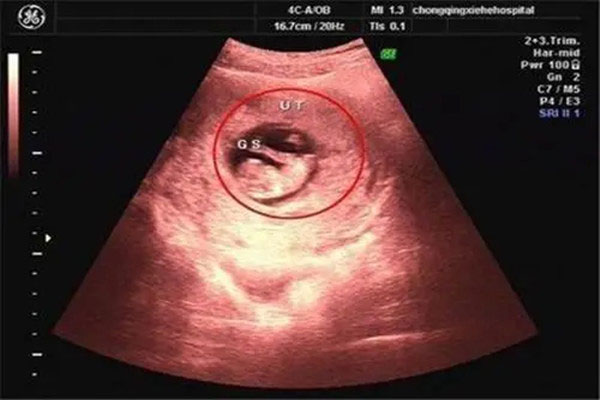

1、查看孕囊数据

B超是目前比较准确的观察男女的方法。当然,医生的结果是最准确的,但是由于国家政策的影响,医生不会告诉马宝关于婴儿的性别。然而,B超检查结束后,医生会给我们一张b超检查单。这张b超表上的数据已经可以解释许多问题。其中之一是孕囊的数据。一般来说,如果孕囊的三个数据呈递减状态,甚至是算术级数,那么就是女孩。如果前两个数据更大,最后一个数据更小,那就是男孩!注意,两个数据不能判断男人和女人!

2、看看孕囊的形状

根据很多宝妈的经验,8周左右的孕囊呈椭圆形或有点像茄子,所以男孩的可能性更大。如果孕囊呈圆形,那么女孩的可能性更大。然而,这受到不同横截面的影响,我们可以进行多次比较!